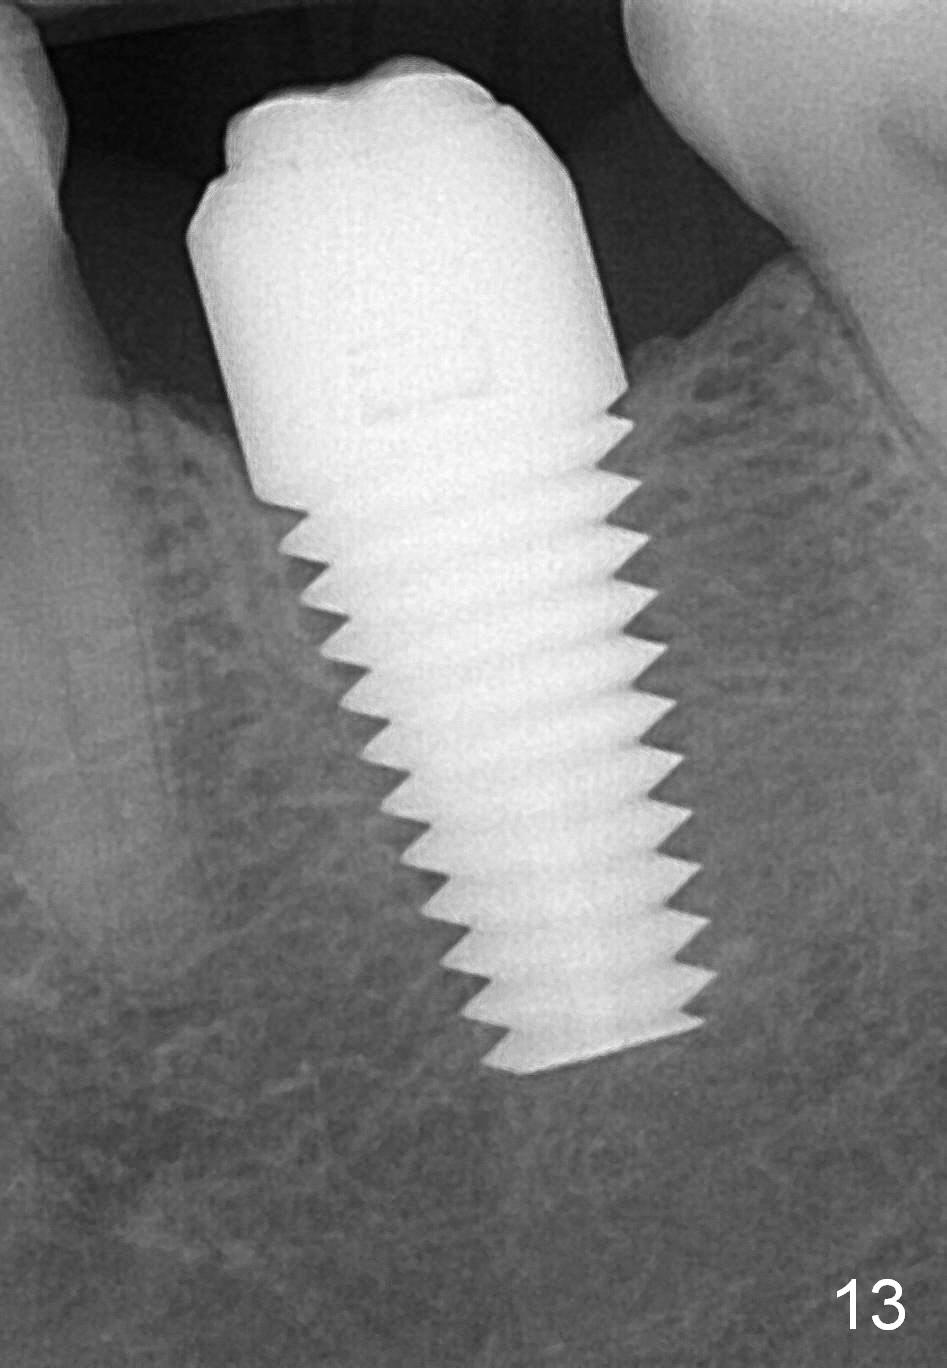

The Emax crown fractures 3.5 years post cementation; there is formation of the apparent lamina dura around the implant (Fig.13). There is no atrophy of papillae when the new crown is cemented (Fig.14 *). There is no bone loss nearly 4 years post cementation (Fig.15).